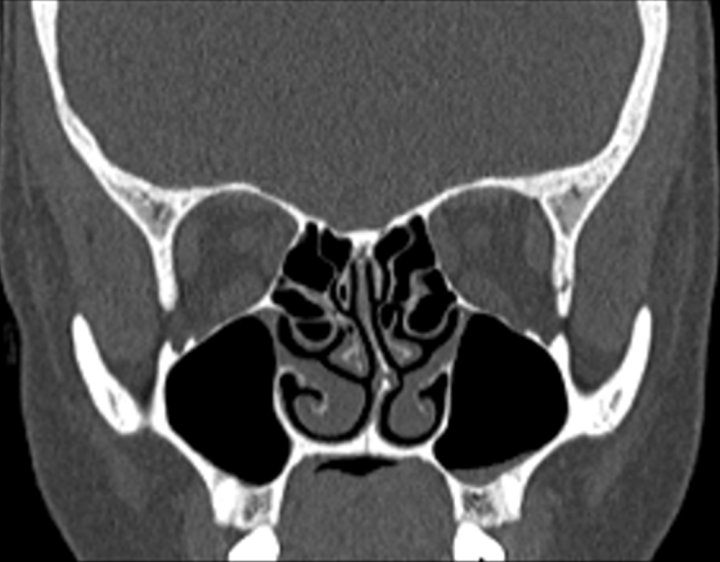

Click any image for labels.